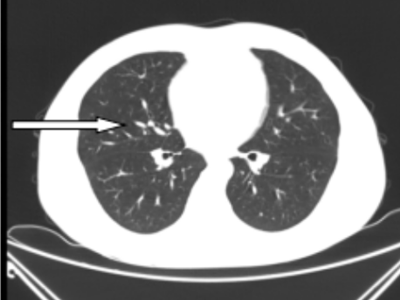

41岁的彭先生,2022年3月份出现咳嗽咳痰,多家立博体育 治疗效果不佳,外院查胸部CT提示肺部占位及大量胸水,且外周血白细胞明显升高及颈部多发的淋巴结肿大。4月初疑诊结核收入立博体育 结核科,入院后发现浅表淋巴结进行性增大,经血液科会诊,考虑淋巴瘤并骨髓侵犯。患者转入血液内科后,行骨髓涂片提示有77%肿瘤细胞,同时请耳鼻喉科行颈部淋巴结切除病检,最终确诊为低级别滤泡性淋巴瘤并肺部、骨髓侵犯(IV期,EZH2基因突变阴性)。4月27日根据最新的滤泡性淋巴瘤诊治指南(NCCN指南及CSCO指南),选用GB方案(奥妥珠单抗联合苯达莫司汀)化疗。第一周期化疗后,彭先生状态良好。5月26日复查肺部CT,肺部占位、胸水及淋巴结明显缩小。咳嗽及气促也完全消失。目前,患者仍在血液内科接受后续治疗。

图二:5月26日第一次化疗后肺部CT,箭头所指的肺实变已消失